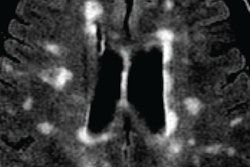

Within the larger study group, 47 children with mono-ADS and 13 with MS underwent MRI using a standardized research protocol on a 1.5-tesla scanner (Twin Speed Excite 12.0, GE Healthcare) to collect data on total brain volume, T1 lesion volume, and T2 lesion volume.

For those children with MS who did partake in strenuous physical activity, their T2 brain lesions had a median size of 0.46 cm3 at MRI, compared with a median size of 3.4 cm3 for those with MS but no strenuous activity. MS patients with strenuous activity also had a median of 0.5 relapses per year, compared with one relapse per year for subjects with no strenuous activity.